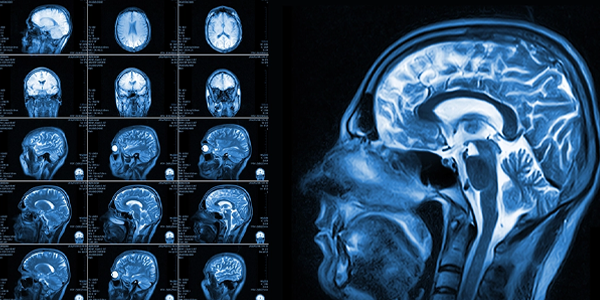

Beyin Anjiyografisine Alternatif Görüntüleme Yöntemleri

Bazı hastalarda anjiyografi yerine aşağıdaki yöntemler tercih edilebilir:

• MR anjiyografi (MRA)

• BT anjiyografi (CTA)

• Doppler ultrasonografi